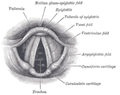

صورة Endoscopic للحنجرة | |

Endoscopic image of larynx seen at the time of intubation of the esophagus during gastroscopy.